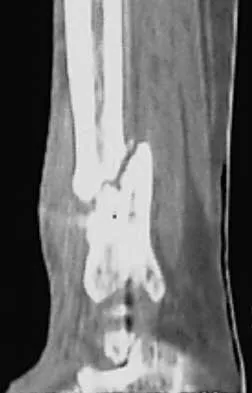

A patient is treated with volar plating for a distal radius fracture. The CT scan shown in Figure 15 is obtained after union of the fracture because the patient reports ongoing symptoms. The prominent hardware is most likely injuring what tendon?

Explanation

Extensor tendon injuries have been reported after volar plating of distal radius fractures. The CT scan shows prominent dorsal hardware a few millimeters ulnar to Lister's tubercle. The second compartment, the ECRL and ECRB, is radial to Lister's tubercle. The ECU runs along the distal ulna. The contents of the fourth dorsal compartment run just ulnar to Lister's tubercle. The EDC tendon is likely irritated in this patient. The EPB runs along the radial border of the radius and is well away from prominent hardware. Benson EC, Decarvalho A, Mikola EA, et al: Two potential causes of EPL rupture after distal radius volar plate fixation. Clin Orthop Relat Res 2006;451:218-222.